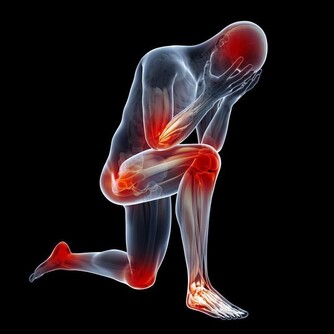

原來常常手麻是一種病!!引起手麻是這些原因.....經常手麻的朋友一定要看!

引起手麻較為常見原因的有以下幾種

手麻的常見症狀

有的人半夜手麻醒來; 有的人晨起手掌僵硬, 麻木, 過一會兒就好了.

有的人拎重物久則手麻, 手掌無力. 有的人拿碗, 一會兒就麻且無力, 不能再拿了.

有的人整天都麻. 有的人整個手掌均麻.有的人1~2 個手指麻. 手麻是一個症狀,

如果影響到日常生活, 就很不方便; 要馬上去看醫生;

如果不影響生活, 也不可以掉以輕心,它往往是一些疾病的先兆. 特別是大腦的問題.

手麻的原因是什麼?